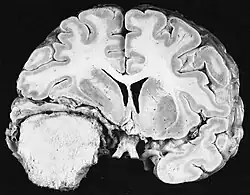

Glioblastoma

Os tumores de células gliais mais comuns e malignos são os glioblastomas. Consistem em uma massa heterogênea de células de astrocitoma pouco diferenciadas principalmente em adultos. Geralmente ocorrem nos hemisférios cerebrais, mais raramente no tronco cerebral ou na medula espinhal. Exceto em casos muito raros, como todos os tumores cerebrais, eles não se estendem além das estruturas do sistema nervoso central.

O glioblastoma pode surgir de uma forma difusa (II. grau) ou um astrocitoma anaplásico (III. grau) se desenvolvem. Neste último caso, é chamado de secundário. No entanto, quando ocorre sem antecedentes ou evidência de malignidade prévia, é referido como primário. Os glioblastomas são tratados com cirurgia, radioterapia e quimioterapia. Eles são difíceis de curar e há poucos casos que sobrevivem além de três anos.

Na ressonância magnética, um tumor intracraniano aparece como uma lesão maciça que pode se tornar mais luminescente após o uso do agente de contraste. No entanto, há sempre uma anomalia de sinal na ressonância magnética, que indica a presença de neoplasia ou edema vasogênico. Normalmente, o aumento da luminescência (realce pelo contraste) é indicativo de um tumor de grau mais alto de malignidade. Um anel contrastante é característico do glioblastoma, com a porção luminescente correspondendo à parte vital do tumor maligno e a área mais escura-hipointense à necrose tecidual.